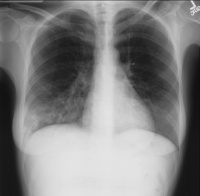

医学肺部体格检查[编辑 | 编辑源代码]

肺部常见的疾病有:气胸肺大泡肺气肿、肺部阴影(严格讲不算单独疾病,但临床上常作为多种肺部占位病变的统称)和肺癌等。

肺炎[编辑 | 编辑源代码]

肺炎是肺实质和间质,由于多种病原体引起其他如放射、化学、免疫、过敏及药物等因素亦能引起肺炎。